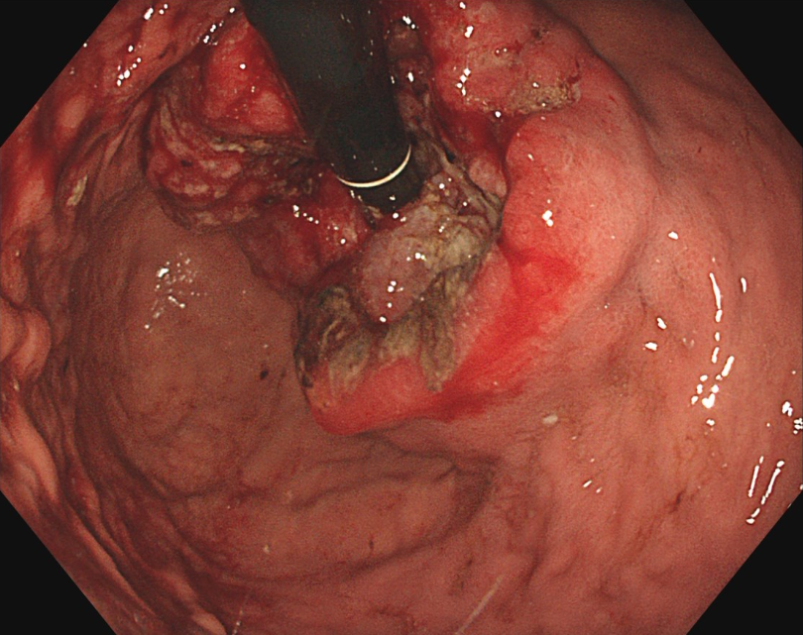

胃カメラを挿入して直接観察する内視鏡検査が行われます。進行度を判断するための検査では、造影CT検査、MRI検査、PET検査などを組み合わせて、がんの深さやリンパ節および周辺臓器への転移がないかを診断します。また、補助的に血液中の腫瘍マーカーの値を見る検査も行います。

内視鏡(胃カメラ)画像

内視鏡的切除

口から挿入したスコープ(カメラ)でがんのある部位を切除します。おなかを切ることがないため、術後の痛みがほぼなく、入院期間も短かく済みます。がんが粘膜内にとどまっている場合のみ適応があり、それよりも進行している場合は手術をはじめとした他の治療が行われます。